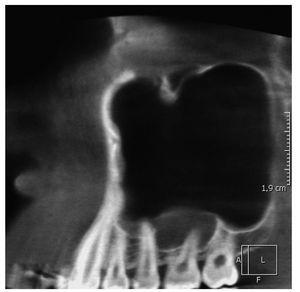

Se obtuvo una tomografía volumétrica digital dental del segundo cuadrante y del seno maxilar suprayacente para continuar el estudio diagnóstico. Por una parte, la TVD confirmó los resultados de la exploración clínica, según los cuales el diente 26 era un diente sano. Por otra parte mostró un ensanchamiento manifiesto de la mucosa basolateral del seno maxilar en craneal de los dientes 26 y 27. Este hallazgo sugirió la existencia de una sinusitis maxilar crónica con localización interseptal (figs. 2 a 4). Se observó además un desplazamiento parcial del orificio natural.

Figura 3. Tomografía volumétrica digital dental: plano sagital.

En imágenes seriadas como la radiografía panorámica se pueden confundir los septos de los senos paranasales con un borde esclerótico. Esta confusión puede llevar al observador a errar el diagnóstico y posiblemente también el tratamiento. La incidencia de estos septos aumenta con la edad y también después de extracciones de molares superiores. Con frecuencia forman nichos de retención que favorecen la aparición de sinusitis.